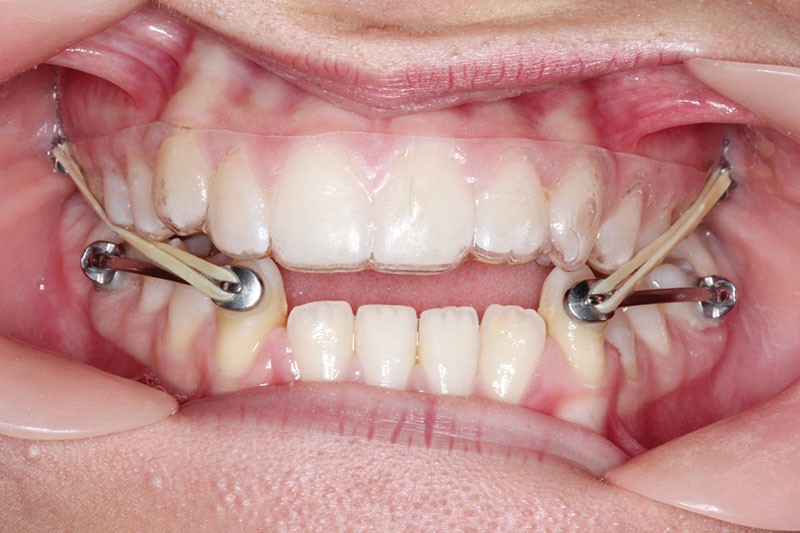

1re phase : recul des secteurs latéraux mandibulaires avec le Motion Classe III Carriere (fig. 4 à 6)

Nous mettons en place des bras latéraux Motion associés à des élastiques intermaxillaires ancrés sur des brackets sur 17 et 27 et une gouttière thermoformée maxillaire portée jour et nuit :

• 1er mois : élastiques 6 oz. 1/4”

• 2e mois et suivants : élastiques 6 oz.1/4“

L’objectif de cette étape est d’obtenir un recul des secteurs latéraux mandibulaires afin de positionner les molaires et canines en classe I et de réorienter le plan d’occlusion en haut en avant.